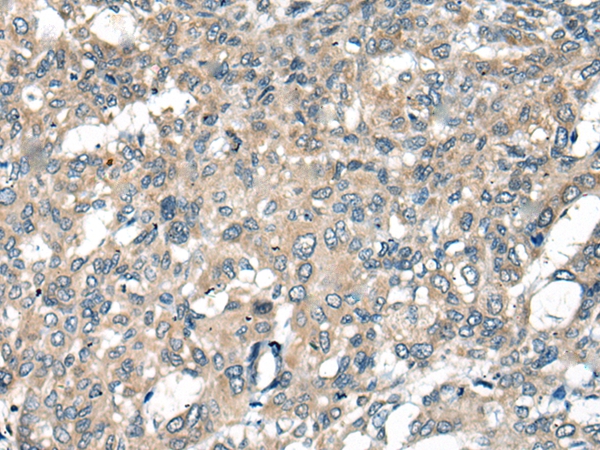

The image on the left is immunohistochemistry of paraffin-embedded Human liver cancer tissue using 46304(ACKR2 Antibody) at dilution 1/45, on the right is treated with synthetic peptide. (Original magnification: x200)